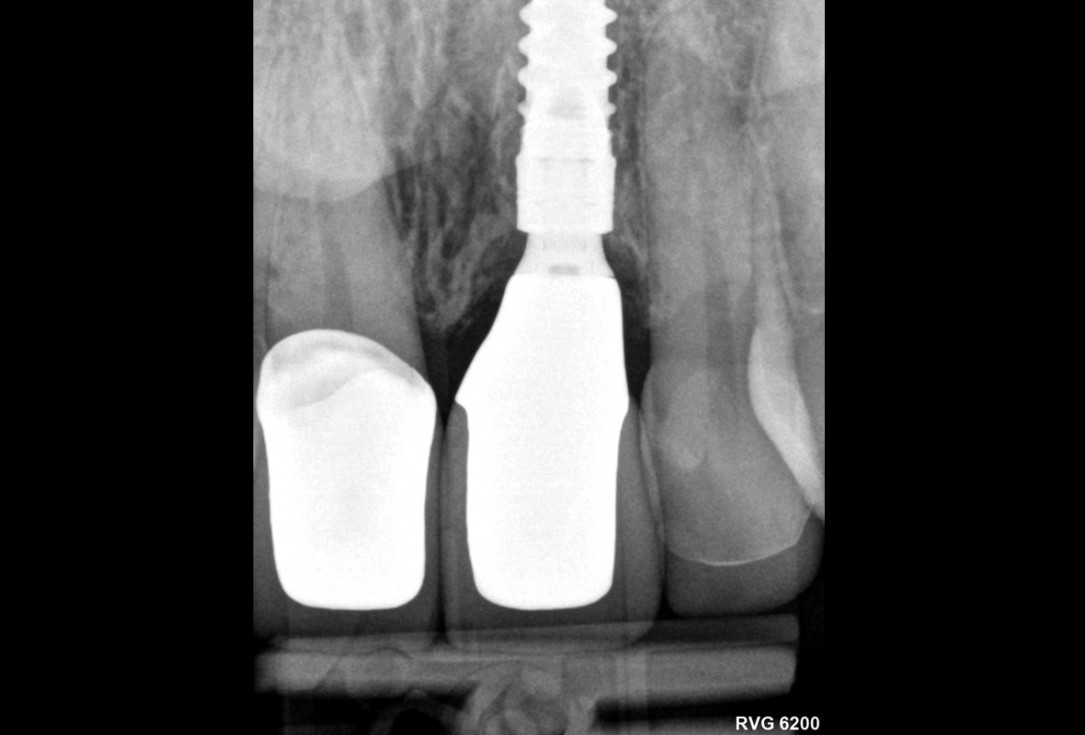

28/30 - Radiological control after surgeryExcellent aesthetic result of buccal augmentation with mucoderm® and maxgraft® after immediate implant placement - 3-years follow-up - Dr. A. Puišys